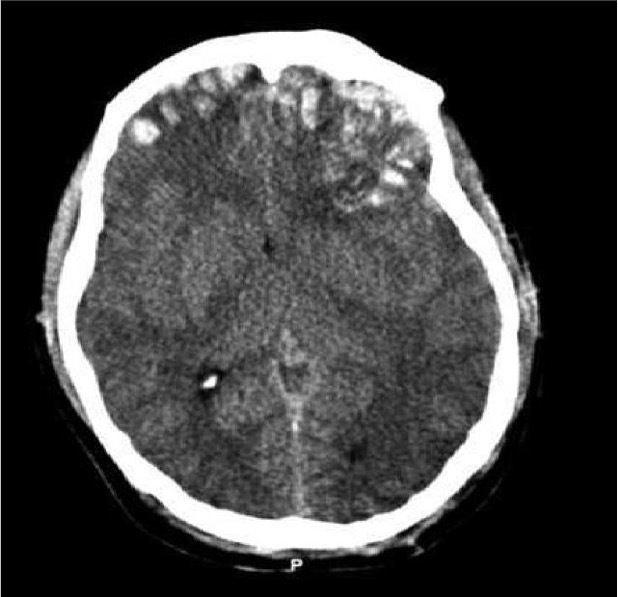

Subdural haematoma

Left subdural with some midline shift

Subdural on CT head